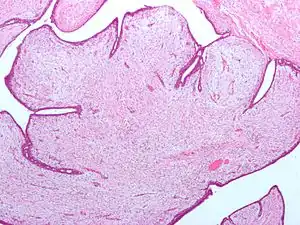

Fibroepithelial neoplasm (Phyllodes tumor).